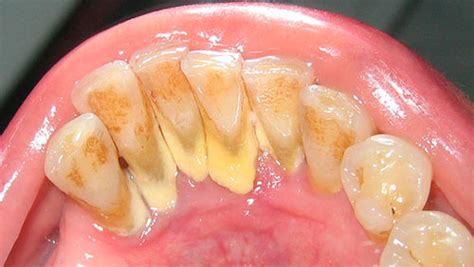

Cuando se cae un trozo de sarro dental, suele indicar acumulación crónica de placa calcificada. Aunque puede parecer un alivio, su caída puede dejar expuesta la encía o una caries. Entendamos qué es el sarro: es esa placa bacteriana que, por falta de higiene adecuada, se endurece y calcifica sobre los dientes (también llamado tártaro dental o cálculo dental). Suele tener un color amarillento o marrón y una textura rugosa. El sarro se adhiere fuertemente al esmalte y no se desprende fácilmente por sí solo con el cepillado normal.

- Ubicación típica: El sarro tiende a formarse especialmente detrás de los dientes inferiores frontales (incisivos inferiores) y en las muelas superiores, porque ahí desembocan las glándulas salivares. La saliva contiene minerales que facilitan la calcificación de la placa. Por eso, no es raro que un “trozo de sarro” provenga de la parte interna de los dientes delanteros de abajo, que es justo donde más se acumula.